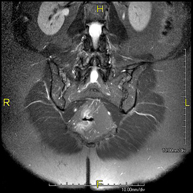

Prova diagnòstica no invasiva que consisteix en l'obtenció d'imatges d'alta definició anatòmica del cerbell mitjançant l'ús d'un camp electromagnètic i ones de ràdio (com un emissor i un receptor). No utilitza radiació ionitzant. Indicacions: problemes vasculars, pèrdua de memòria, epilèpsia, cefalea, malformacions, sospita de tumor, meningitis. - RM de Cais

Prova diagnòstica no invasiva que consisteix en l'obtenció d'imatges d'alta definició anatòmica de l'oïda interna mitjançant l'ús d'un camp electromagnètic i ones de ràdio (com un emissor i un receptor). No utilitza radiació ionitzant. Indicacions: problemes auditius, mareigs, vertigen. - RM de Coll

Prova diagnòstica no invasiva que consisteix en l'obtenció d'imatges d'alta definició anatòmica del coll mitjançant l'ús d'un camp electromagnètic i ones de ràdio (com un emissor i un receptor). No utilitza radiació ionitzant. Indicacions: sospita de tumor, infeccions, ganglis. - Angio-RM intracranial

Prova diagnòstica no invasiva que consisteix en l'obtenció d'imatges d'alta definició anatòmica de les artèries cerebrals mitjançant l'ús d'un camp electromagnètic i ones de ràdio (com un emissor i un receptor). No utilitza radiació ionitzant. En la majoria dels casos és necessari l'us de contrast paramagnètic (Gadolino). Permet un estudi angiogràfic no invasiu gràcies a la injecció de Gadolino amb una reconstrucció posterior en 2D i 3D gràcies a estacions de treball especialitzades. Indicacions: malformacions vasculars, aneurismes d'artèries cerebrals, arteriosclerosi. - Angio-RM de troncs supraaòrtics

Prova diagnòstica no invasiva que consisteix en l'obtenció d'imatges d'alta definició anatòmica de les artèries caròtides i vertrebrals a nivell de coll mitjançant l'ús d'un camp electromagnètic i ones de ràdio (com un emissor i un receptor). No utilitza radiació ionitzant. En la majoria dels casos és necessari l'us de contrast paramagnètic (Gadolino). Permet un estudi angiogràfic no invasiu gràcies a la injecció de Gadolino amb una reconstrucció posterior en 2D i 3D gràcies a estacions de treball especialitzades. Indicacions: problemes circulatoris cerebrals, síncope. - RM espectroscòpia cerebral